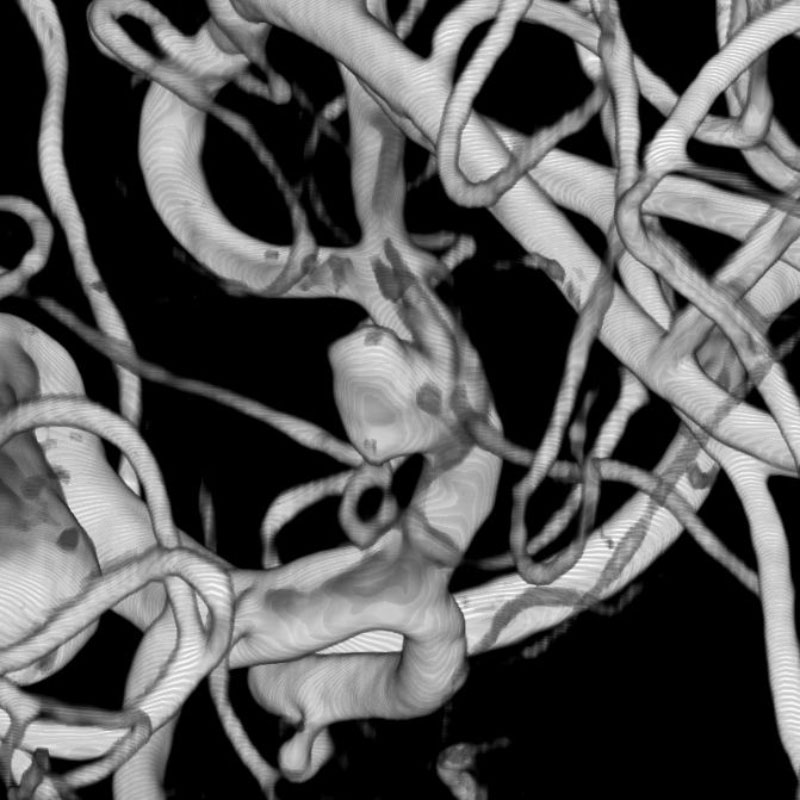

脳底動脈瘤

クリッピング術

手術前

クリップ前

クリップ後